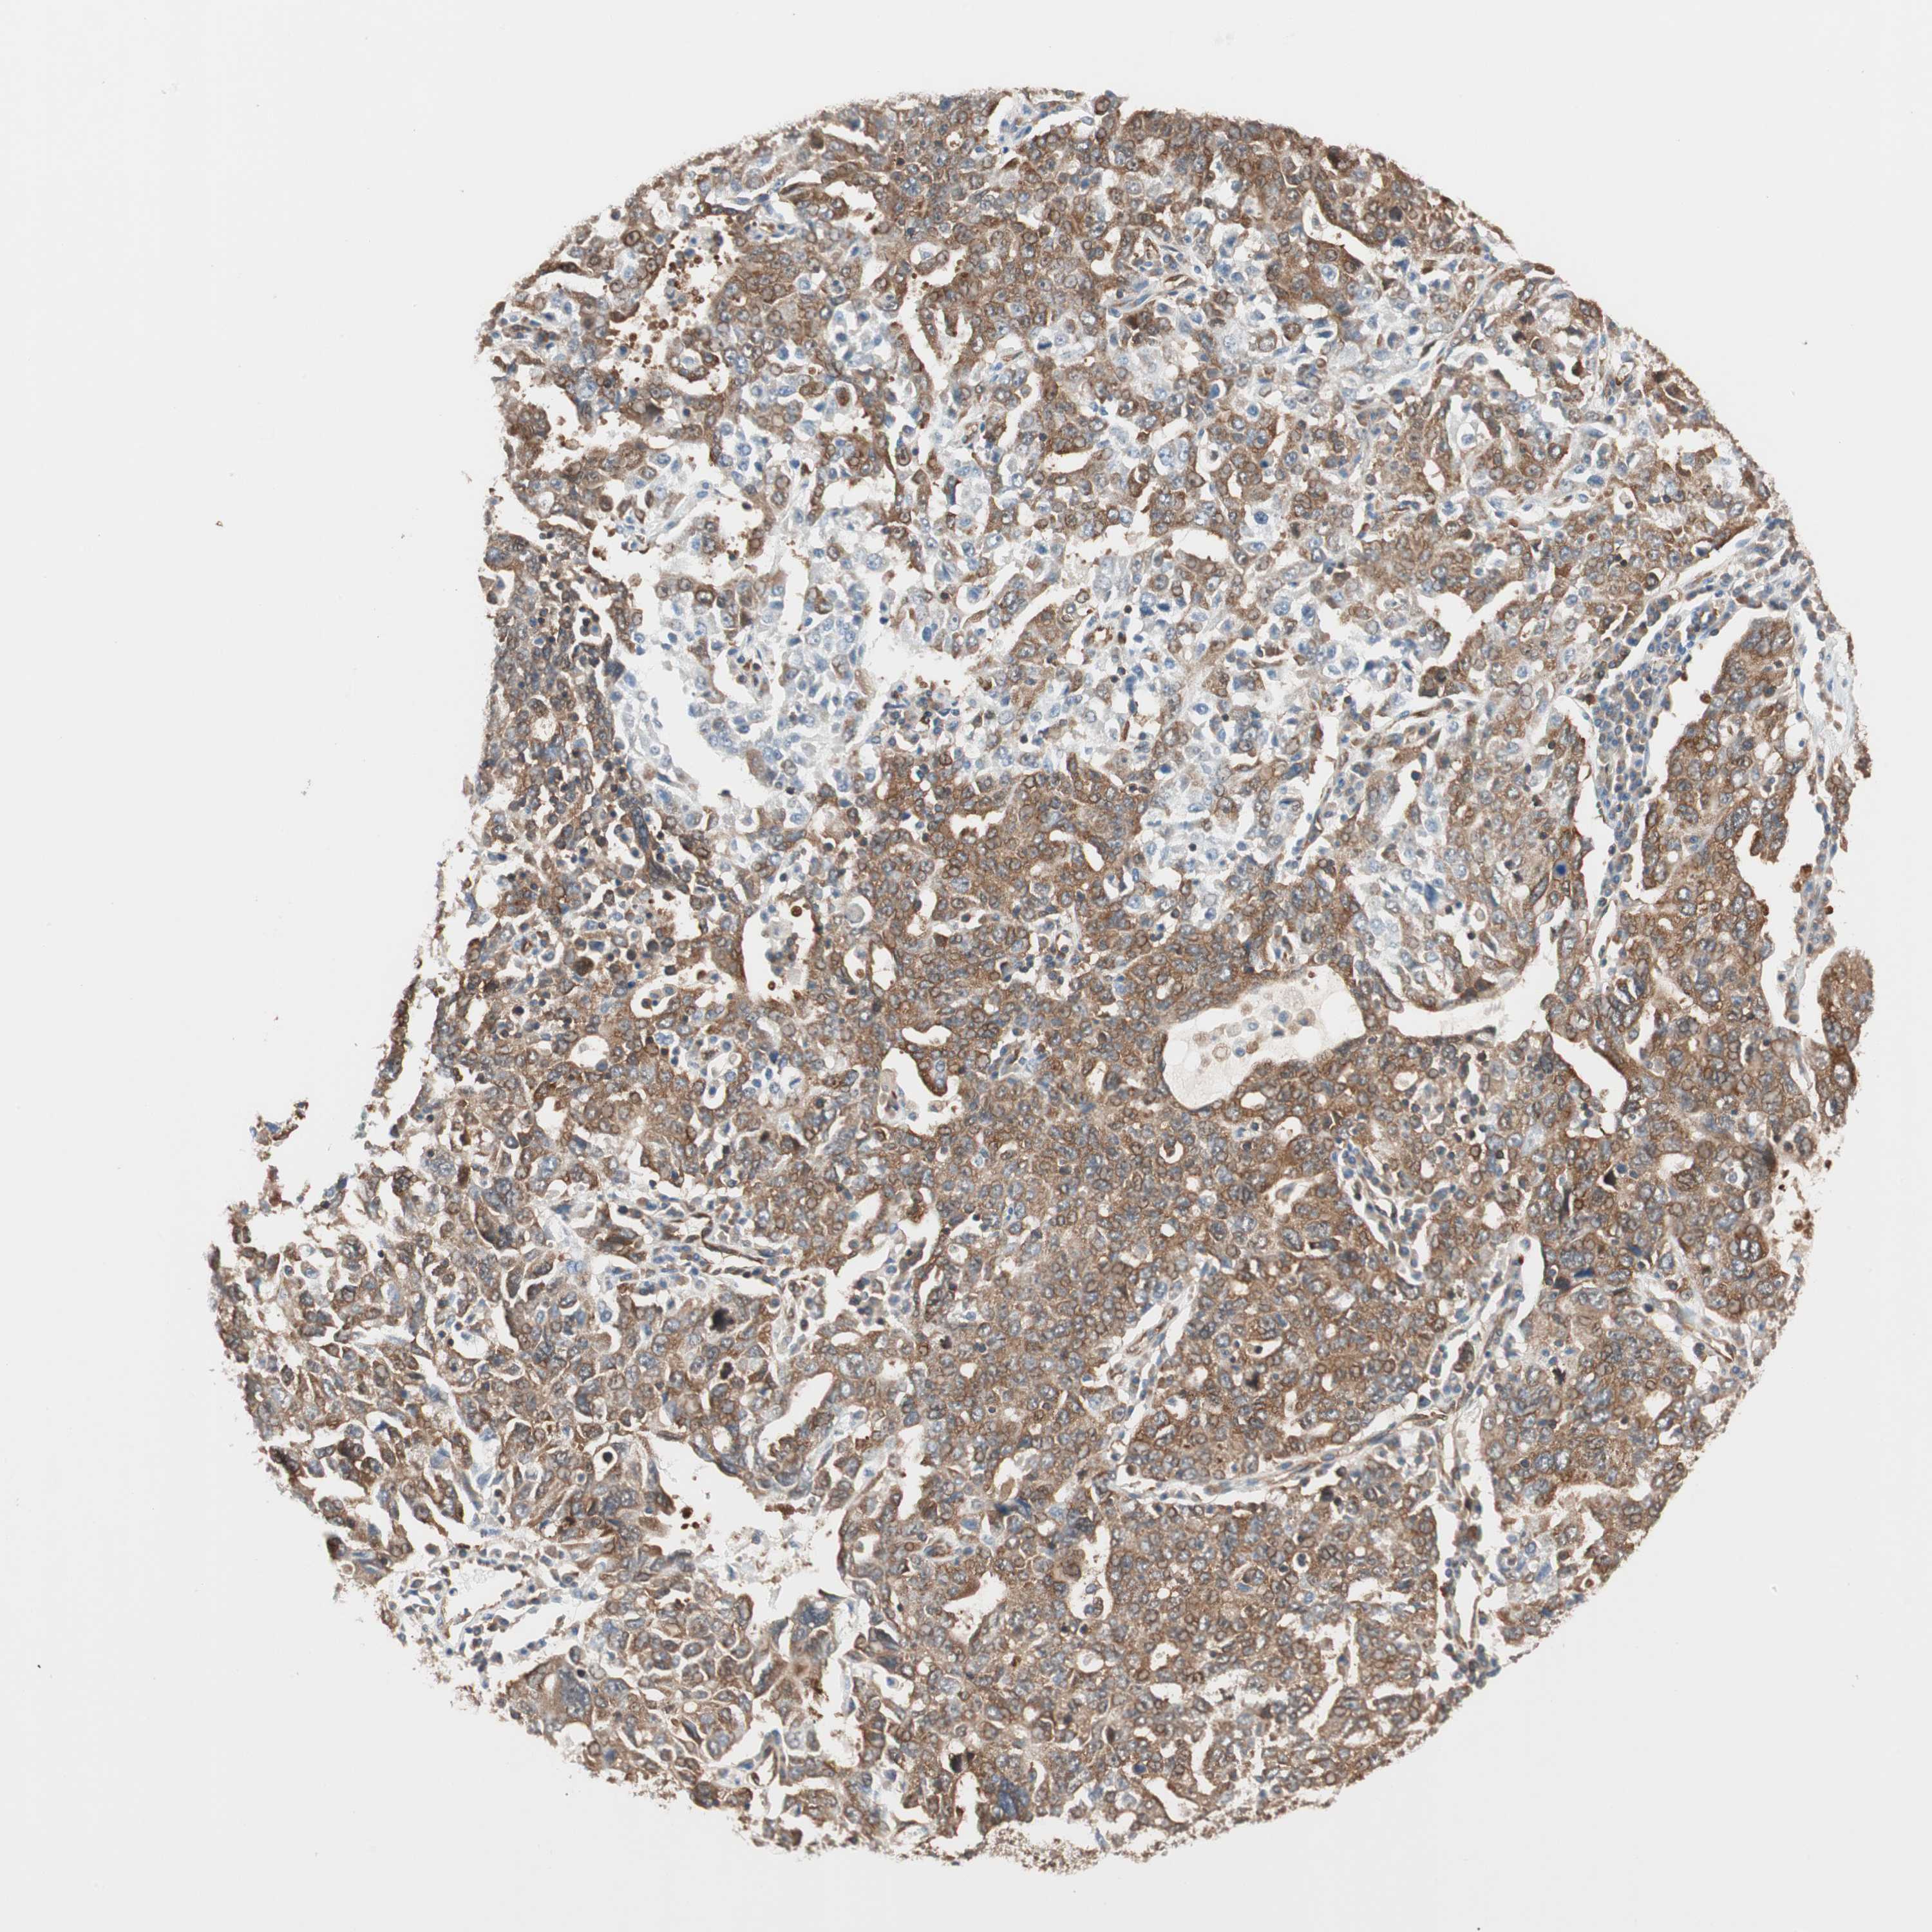

OVARIAN CANCER - Protein expressioni

A mouse-over function shows sample information and annotation data. Click on an image to view it in a full screen mode. Samples can be filtered based on level of antibody staining by selecting one or several of the following categories: high, medium, low and not detected. The assay and annotation is described here.

Note that samples used for immunohistochemistry by the Human Protein Atlas do not correspond to samples in the TCGA dataset.

Antibody stainingi

Antibody staining in the annotated cell types in the current human tissue is reported as not detected, low, medium, or high, based on conventional immunohistochemistry profiling in selected tissues. This score is based on the combination of the staining intensity and fraction of stained cells.

Each image is clickable and will lead to virtual microscopy that enables deeper exploration of all samples and also displays staining intensity scores, fraction scores and subcellular localization as well as patient and tissue information for each sample.

Antibody HPA005750

Antibody CAB005399

Cystadenocarcinoma, serous, NOS